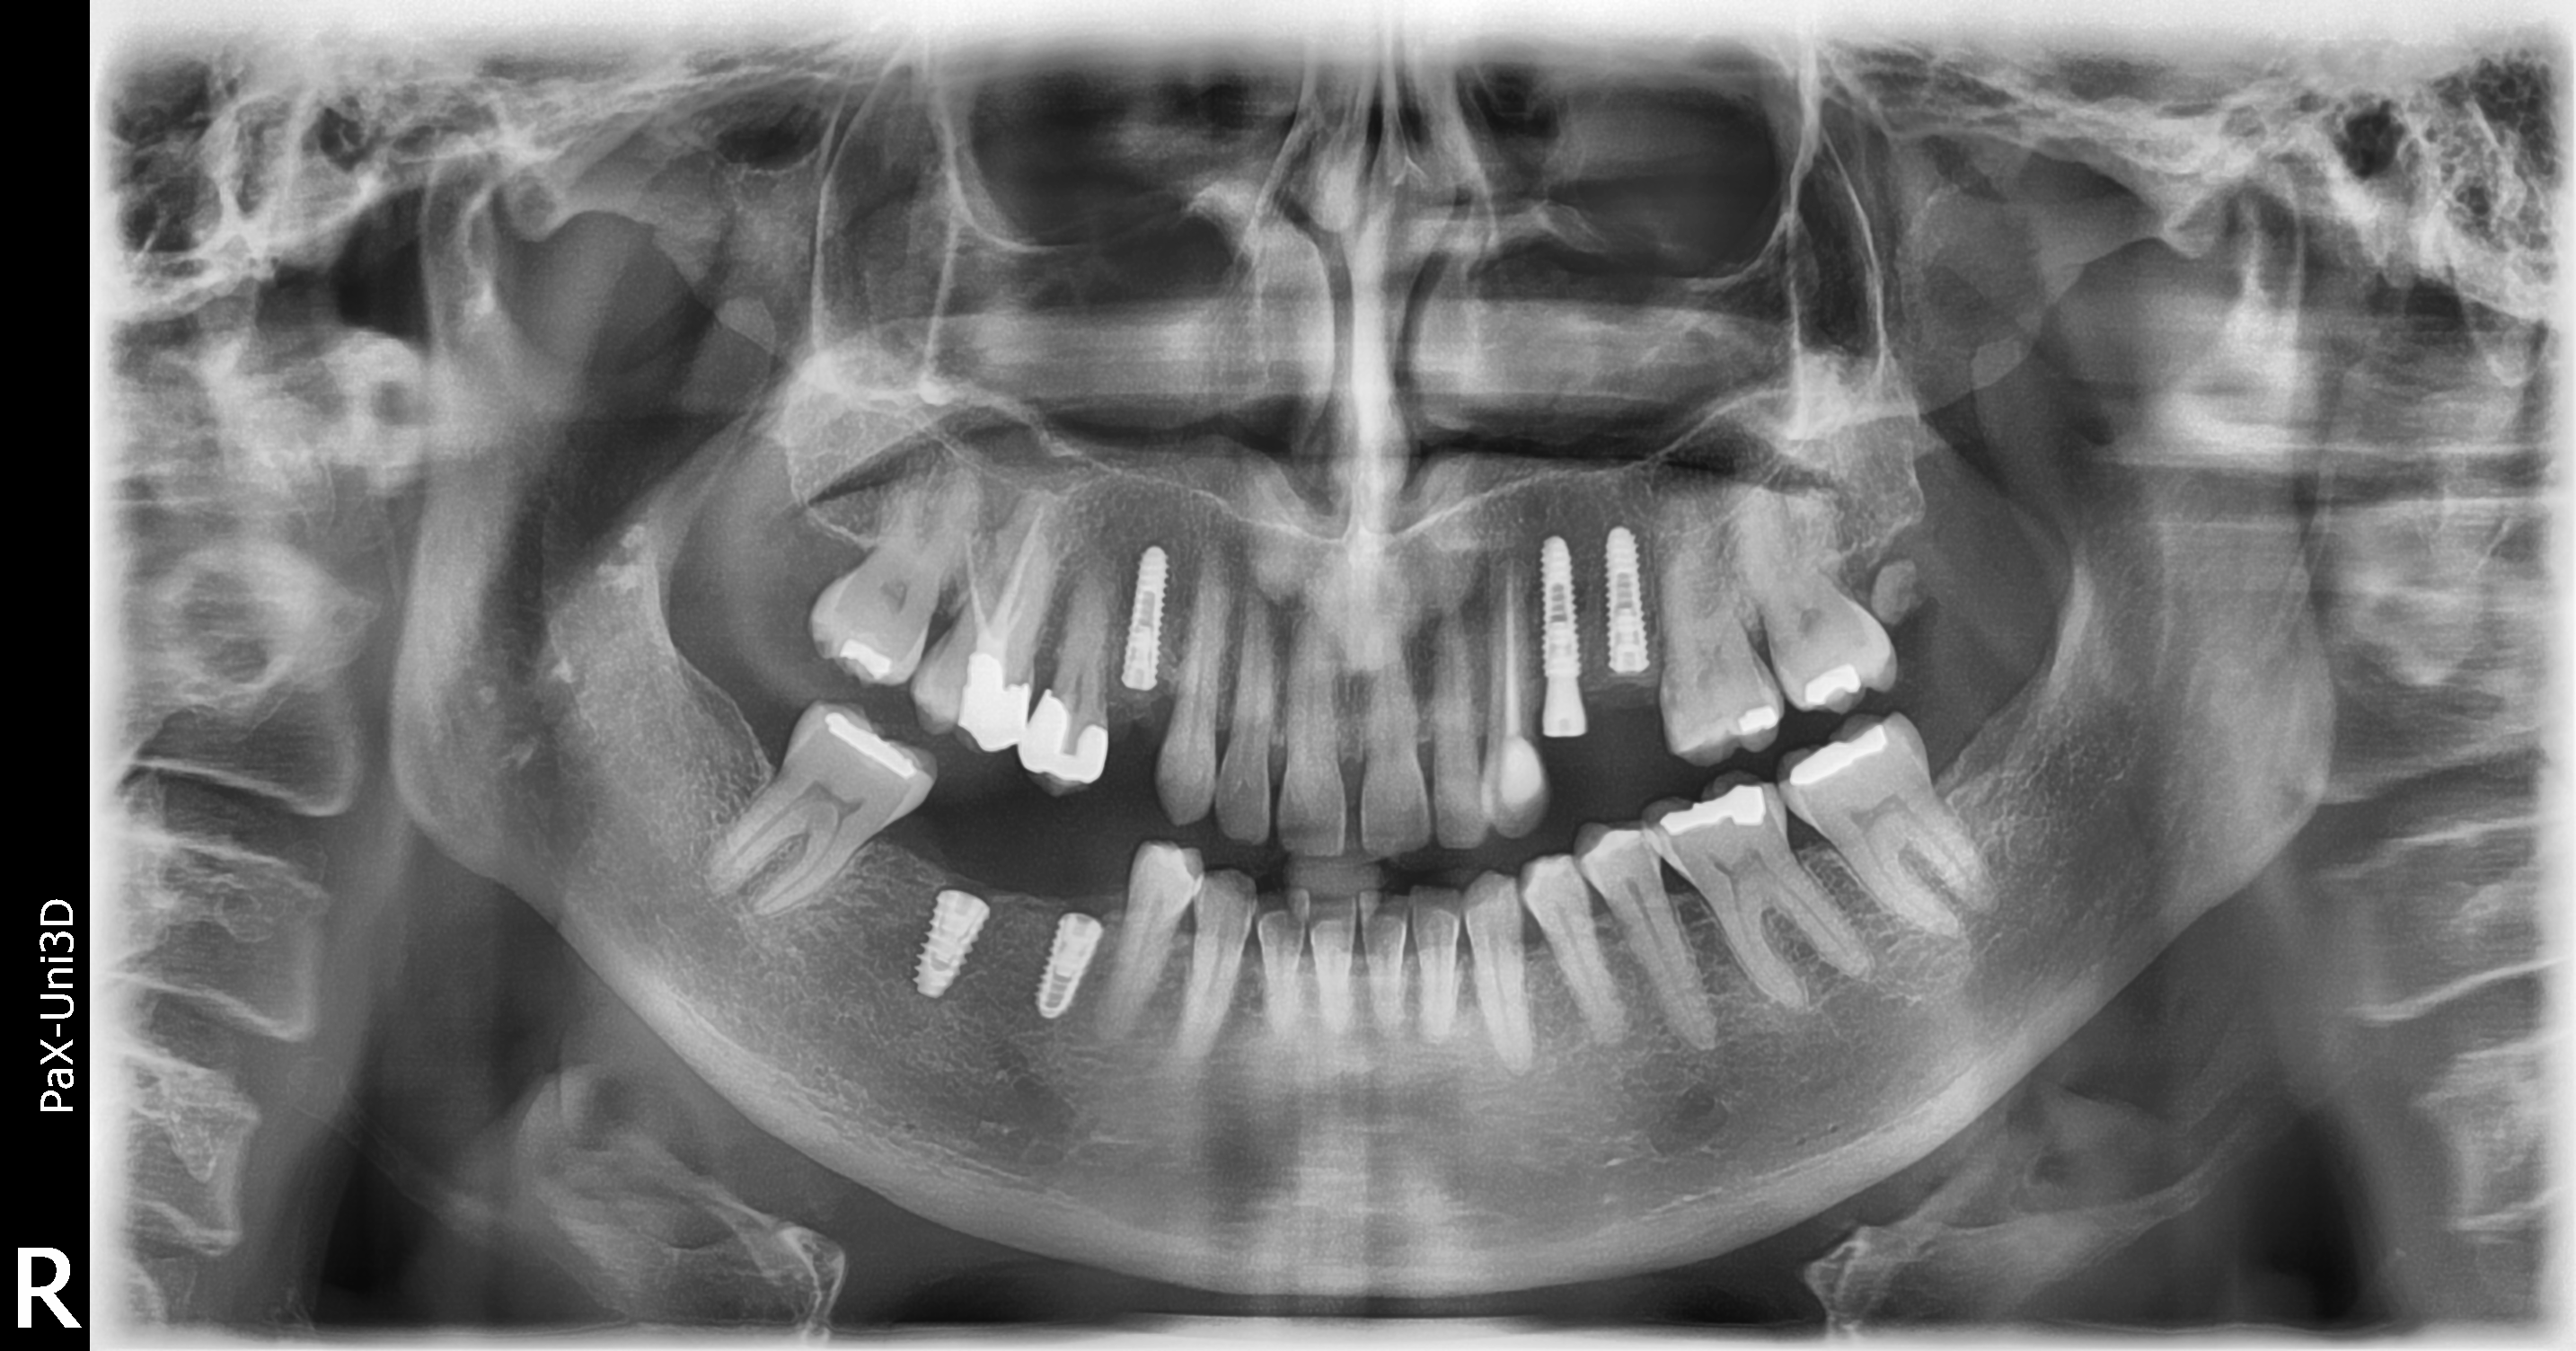

At Carvolth Dentistry in Langley, we initiate your journey with a detailed examination, leveraging cutting-edge imaging to assess bone density and plan the implant placement.

With the help of CBCT and Intra Oral scan, we make treatment plan suitable for you. Either surgery with a surgical guide or free hand.

With state-of-the-art equipment and expertise, we surgically place the titanium implant post into the jawbone, ensuring stability and optimal positioning.

Dental implants have revolutionized the realm of restorative dentistry, offering a robust solution for missing teeth. At Carvolth Dentistry in Langley, we’re passionate about educating our patients on this transformative procedure. Whether you’re curious about the intricacies of the implant process or the materials utilized, our team stands ready to illuminate every facet. Dive deep into the world of dental implants with us, understanding their advantages, the technology behind them, and how they can serve as a foundation for a rejuvenated smile.